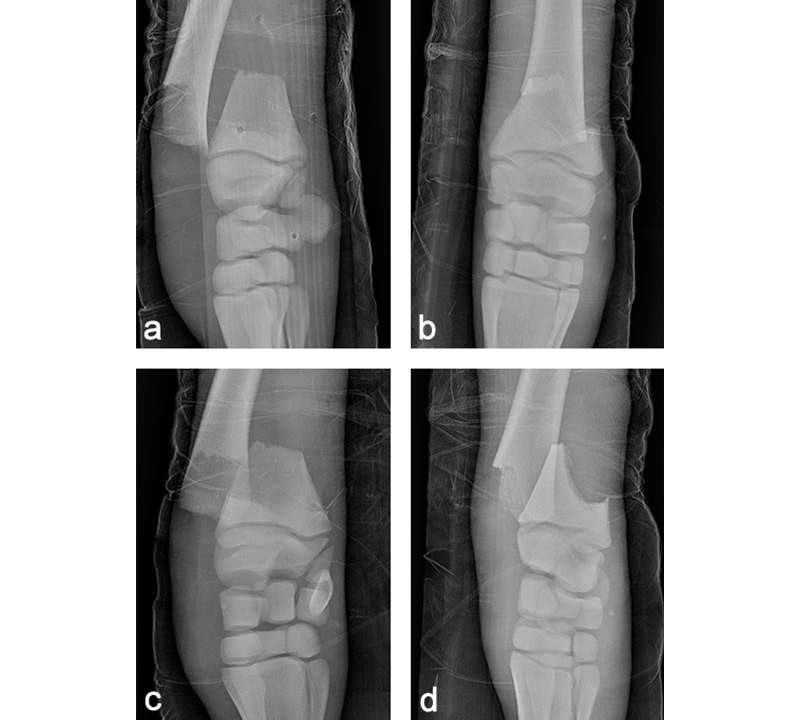

A 68 kg Warmblood foal was presented for evaluation and treatment of a complete open fracture of the left distal radius sustained during parturition 4 hours earlier. The fracture had occurred when the mare laid down against the wall of the stables while the foal was partially through the birth canal. The foal had been recumbent since birth. The limb had been partially stabilized with a full limb bandage and lateral splint prior to admission. The radiographs confirmed the presence of a complete slightly oblique (proximomedial to distolateral) open fracture, just proximal of the distal radial physis (Fig 10). Extensive maceration of the medial soft tissues just proximal of the carpus was noted, with a 0.5 cm full thickness skin laceration. The foal was stabilized and was taken to surgery a few hours following admission.

The foal was anesthetized and placed in dorsal recumbency. The left forelimb was placed in extension, clipped, prepared, and draped for aseptic surgery. A cranial approach to the distal aspect of the radius was made. The fracture was reduced, and a 6-hole LCP Equine T-Plate 4.5 was placed beneath the extensor carpi radialis (Fig 11). Two 5.0 mm locking screws were placed in the horizontal portion of the plate to engage the distal portion of the radius, just proximal of the distal radial physis. A 4.5 mm cortex screw was then placed into the second hole of the shaft of the plate, to provide interfragmentary compression and compress the plate to the proximal portion of the bone. The remaining holes were filled with 5.0 mm locking screws. The presurgical planning had included placing a second lateral LCP plate, however, the foals physiological status deteriorated. Further fracture fixation was therefore abandoned, and the surgery site was closed. A tube cast was placed from the level of the fetlock to the proximal radius. The foot and pastern were left free to minimize flexor tendon laxity. The foal was placed in sternal recumbency and required 2 hours of assisted ventilation before she started to breath spontaneously. Following surgery, she stood unassisted and was able to ambulate and suckle.

Postoperatively, the foal was noted to have a moderate carpus valgus deformity. Radiographic assessment, however, showed that the lateral deviation was not due to malalignment of the fracture. A gradual improvement in the degree of valgus deformity has been seen with growth as the foal has matured (Fig 13). Radiographic healing of the fracture has proceeded quickly with very little callus formation (Fig 14).